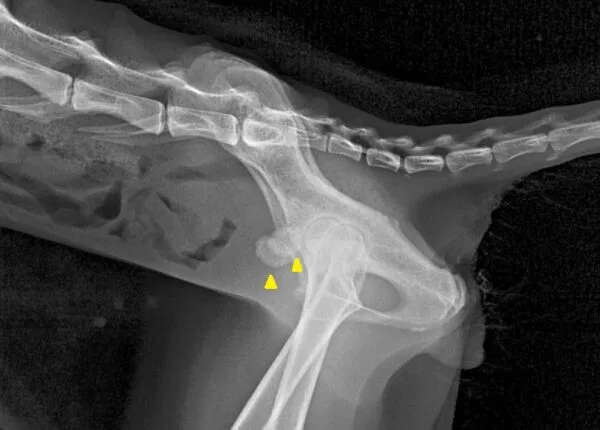

◆ 難しいケース

・小さな石が無数に存在。数も形も多様で摘出が困難である

・レントゲン撮影を何度も繰り返し、残存石のチェックが必要である

・骨盤の骨と陰影が重なり、画像検査での完全な描出が困難になることもある